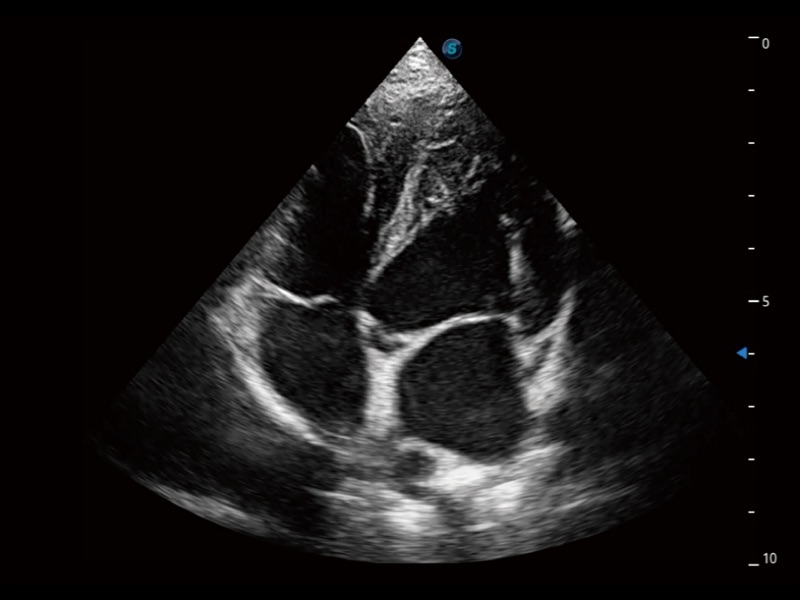

动物是人类最亲密的朋友和最值得信赖的伙伴。DB中国旗舰官方网站也一直致力于探索动物专用的超声影像解决方案。全新推出的ProPet系列,是DB中国旗舰官方网站在动物超声影像智能化、专业化、精准化的一次跨越式革新。动物不能用言语来表述自己的不适,通过超声影像,ProPet系列搭建了动物医生与不同物种沟通的“桥梁”,为动物医生注入了“治愈之力”。 ProPet 70将是您值得信赖的超声伙伴。它配备了复合材料线阵探头,帮助动物医生获得卓越精准的临床图像。同时ProPet 70直观便捷的操作体验以及专业的测量工具,可为不同体型和生理结构的动物带来全面临床评估,切实为动物医生提供智能、专业、精准的超声影像解决方案。

ProPet 70 进一步提升了微米成像算法,更加注重对基础原始图像的还原和保留,在有效减少斑点噪声、增强组织边界显示的同时,避免过度优化丟失真实的解剖信息。

ProPet 70专为动物医生设计,对不同的动物体型和生理结构作出了针对性的优化。通过动物影像专用软件,可满足个性化的应用需求,帮助动物医生获得更精确的诊断数据。

ProPet 70 全新的动物超声智能软件和丰富的探头群,为动物医生提供了高清晰度和精细分辨率的图像,无论在宠物、马科、畜牧还是实验室动物等应用中都可以轻松应对,为您的日常工作带来满意的体验。